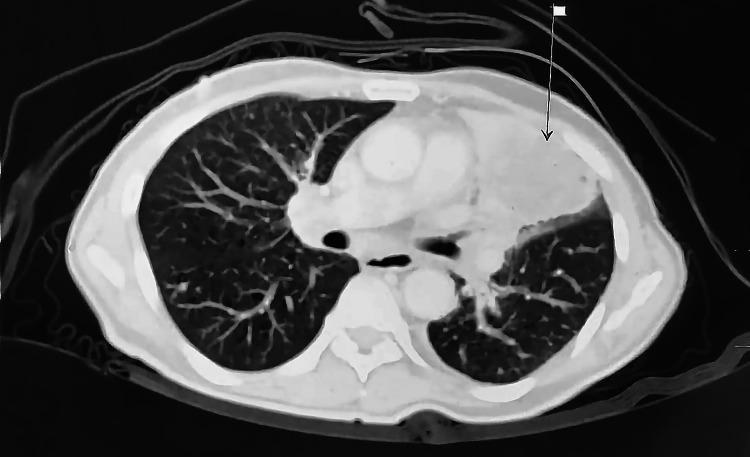

我们报告了沙特阿拉伯首例通过逆转录-聚合酶链反应技术证实存在 Kirsten 大鼠肉瘤病毒癌基因同源物(KRAS)G12C 突变的两例肺腺癌患者的病例系列。两名患者均为男性,年龄分别为 64 岁和 76 岁。第一名患者有重度吸烟史,而第二名患者未报告任何吸烟史。两例患者的肿瘤亚型均被确定为非黏液性肺腺癌。较年轻的患者表现为全身淋巴结肿大和右侧肺部肿块病变,而较年长的患者表现为 III - A 期左肺腺癌,需要快速治疗。对第一例病例的初步检查显示右侧纵隔移位、双侧颈部淋巴结肿大,以及右锁骨上核心活检的低分化肿瘤,导致采用姑息治疗并定期检查。第二例病例在确认生命体征稳定且实验室检查(中性粒细胞 100)后无发热症状。需要进一步开展研究,特别是针对大量来自阿拉伯湾地区的患者,以确认本国人群与国际人群之间的显著差异。此外,未来的研究应调查阿拉伯湾地区患者与其他患者之间 KRAS 突变型肺腺癌分化方面的更多差异。